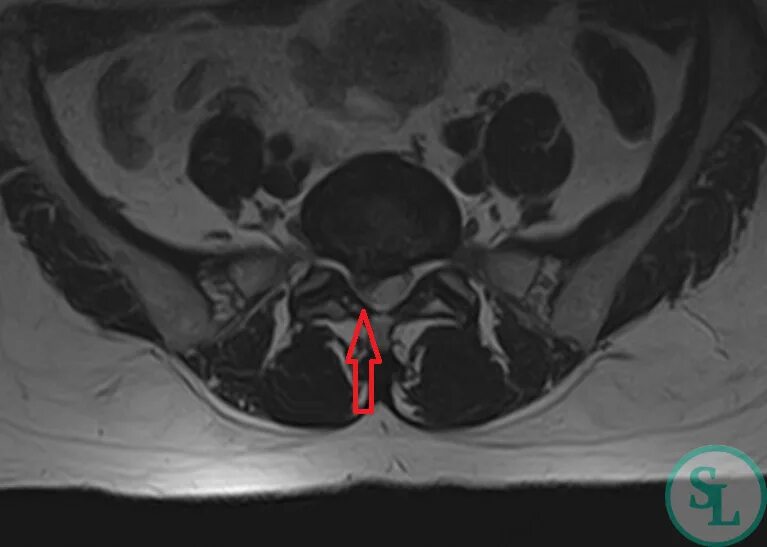

Грыжа экструзия диска l5 s1